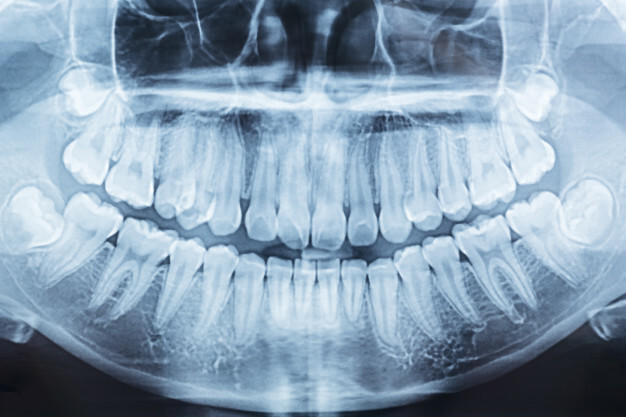

Многоступенчатое обезболивание, рентгенодиагностика, собственно удаление с использованием, возможно, хирургической методики, письменные рекомендации, обязательные повторные контрольные осмотры.